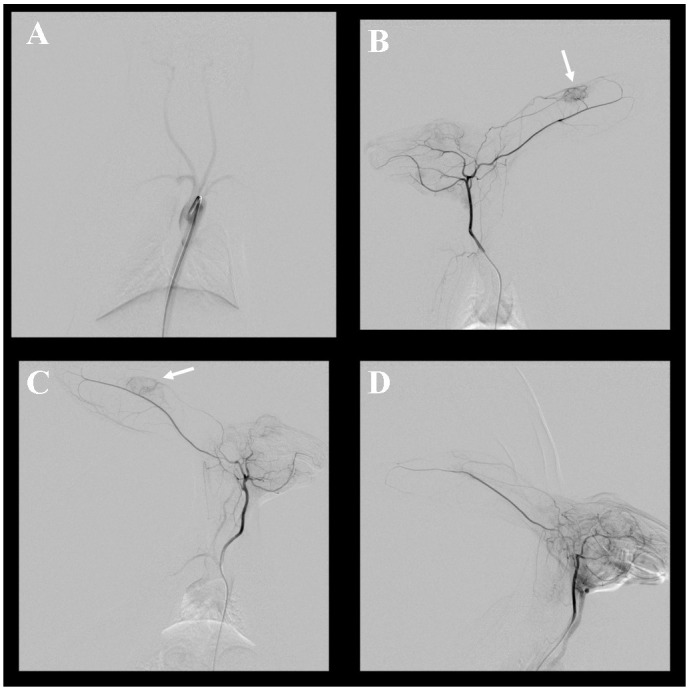

本研究旨在探讨兔耳廓VX2肿瘤作为动脉内栓塞实验模型的可行性。本研究已获我们的机构动物护理和使用委员会批准。将VX2肿瘤植入12只新西兰大白兔双耳。接种后1 ~ 2周行血管造影、超声、热像检查,观察血管造影及病理特征,并进行图像分析。之后处死动物,由病理学家进行组织学分析。12只实验兔3/24耳未见肿瘤生长,1只兔在超声检查麻醉时死亡。因此,总共获得了19个耳廓的图像。11只家兔均成功行血管造影,所有肿瘤均可见血管增生及肿瘤供血血管。随着体积的增大,增强效果显著增强。组织学检查,平均坏死面积为27%。结论:兔耳廓VX2肿瘤模型易于制作,视觉检查可方便地观察其特征。血管造影显示血管增生,肿瘤供血血管易接近。因此,对动脉内栓塞的研究具有重要意义。

This study aimed to evaluate the feasibility of VX2 tumor in rabbit auricles as an experimental model for intra-arterial embolization. This study was approved by our Institutional Animal Care and Use Committee. VX2 tumors were implanted in both auricles of 12 New Zealand White Rabbits. To investigate the angiographic and pathologic characteristics, angiography, ultrasonography, and thermography were performed 1-2 weeks after inoculation, and image analysis was performed. The animals were sacrificed thereafter, and histologic analysis was conducted by a pathologist. Tumors did not grow in 3/24 auricles of 12 rabbits used in the experiment, and one rabbit died during anesthesia for an ultrasonographic examination. Therefore, images were obtained from a total of 19 auricles. Angiography was successfully performed in 11 rabbits, and hypervascularity and tumor feeding vessels were clearly observed in all tumors. The enhancement effect increased significantly as the volume increased. In histologic evaluation, the average area of necrosis was 27%. In conclusion, a rabbit auricular VX2 tumor model is easy to create, and its features can be conveniently observed on visual inspection. Moreover, it appears hypervascular on angiography, and the tumor feeding vessel is easy to approach. Thus, it is useful for studying intra-arterial embolization.